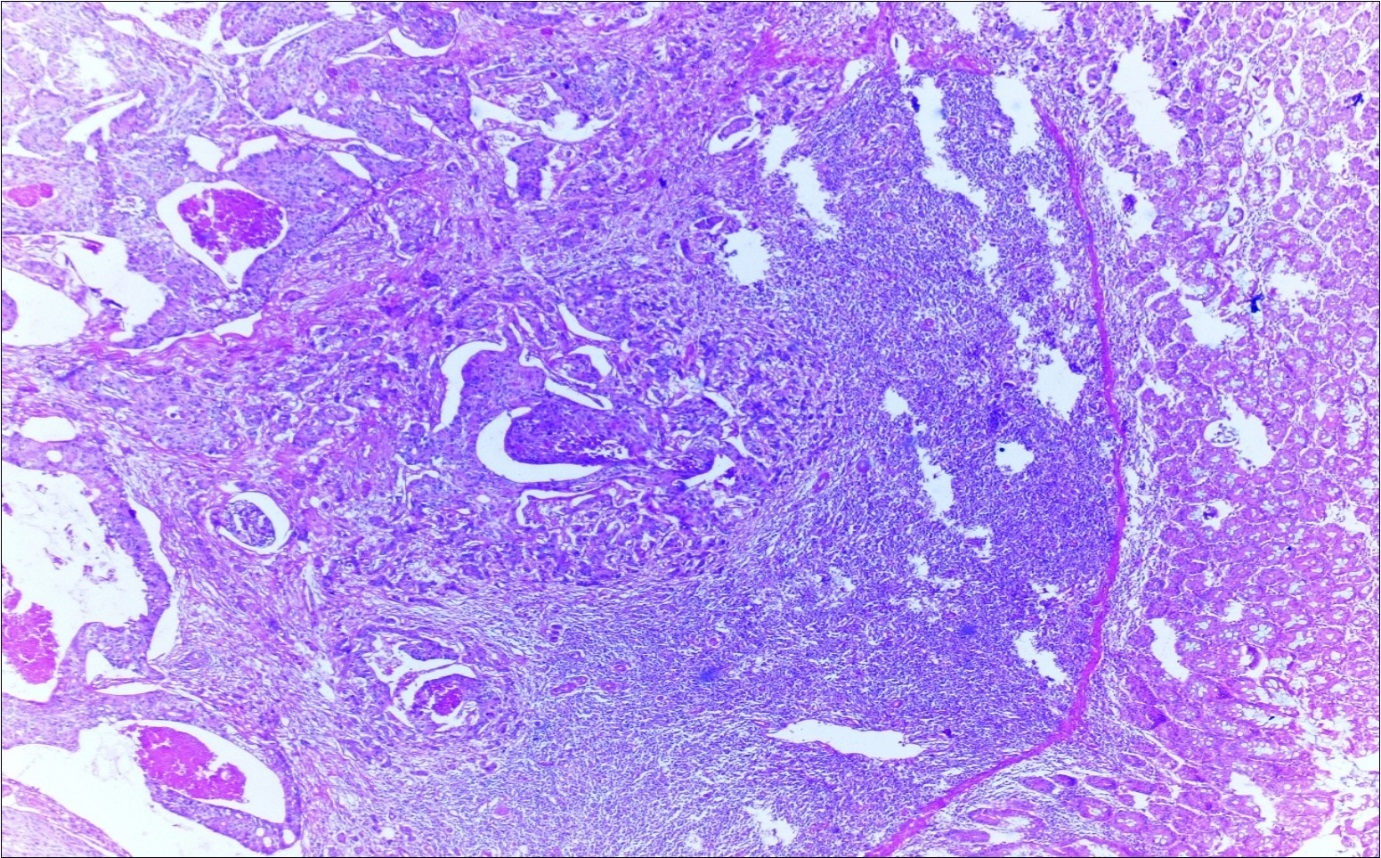

A 63-year-old woman presented to the Department of General Surgery as an outpatient with abdominal pain. Physical examination showed the signs of acute appendicitis and appendectomy was performed. During microscopic examination, a small focus of atypical monotonous lymphoid cell population was seen and the material was sampled totally. The pathological examination revealed MALT lymphoma (Figure 1), with diffuse positivity of cluster of differentiation (CD) 20 (Figure 2), CD 79a and B-cell lymphoma (Bcl- 2) (Figure 3) with just a few CD3 positive lymphoid cells. However, no evidence of adenocarcinoma was found in the appendectomy specimen. After the diagnosis of lymphoma, a complete colonoscopy was planned and this revealed a solid tumoral mass in the caecum measuring 5x4x4 cm. Computed tomography of the abdomen and pelvis revealed mesenteric lymphadenopathy associated with a mass in the caecum with multiple nodules in liver consistent with metastasis (Figure 4). Frozen sections were not obtained since the treatment method would not be affected. The patient underwent anterior resection with regional lymphadenectomy, with the pathological assessment of the resected specimen revealing a collision tumor consisting of a poorly differentiated adenocarcinoma extending through the muscularis propria with MALT lymphoma (Figure 5). Microscopic evaluation of the 11 regional lymph nodes in the mesentery of the resected colon and liver biopsy showed diffuse infiltration of MALT lymphoma with metastasis of adenocarcinoma (Figure 6). According to immunohistochemistry, atypical lymphocytes were positive for CD 20, Bcl-2, and negative for CD3, CD5, CD10, CD23, Bcl-6, terminal deoxynucleotidyl transferase, and cyclin D1. The proliferation fraction (MIB-1 immunostaining) was approximately 20%. The morphological and immunohistochemical findings were used to confirm the diagnosis of synchronous presentation of MALT lymphoma and colon adenocarcinoma within the caecum, mesenteric lymph nodes and liver metastases.

Figure 5.Adenocarcinoma with MALT lymphoma infiltration of colon (h&e;200)

Figure 6.Adenocarcinoma with MALT lymphoma infiltration of lymph node (h&e;200)